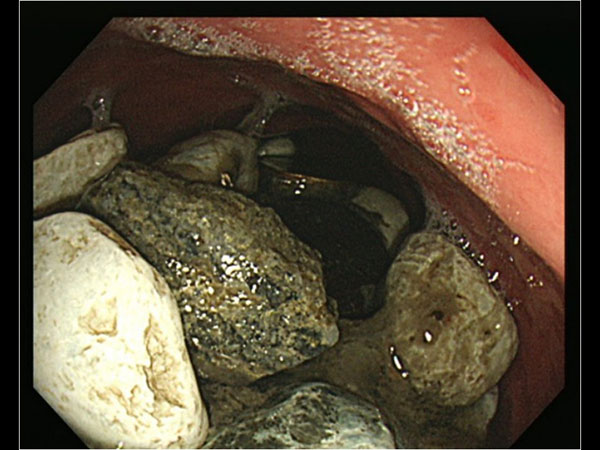

உடனே இதை தாமதித்தால் உயிருக்கே ஆபத்தாகிவிடும் என்று உணர்ந்த மருத்துவர்கள் உடனடியாக அறுவை சிகிச்சை செய்தார்கள். இது மிகவும் சவாலான சிகிச்சையாகவே அவர்களுக்கு இருந்தது. கற்கள் எங்கெல்லாம் சென்று அடைந்திருக்கின்றன என்பதே குழப்பமாக இருந்தது. கேஸ்டிரோதெரபி மூலம் பொருளை வெளியேற்ற முடிவு செய்தனர்.

வெவ்வேறு அறுவை சிகிச்சை வழிமுறைகளைப் பயன்படுத்தி, வாய்வழியாக மிக மெல்லிய டியூபை வயிற்றுக்குள் செலுத்தி உடலின் உள்ளுறுப்புக்களில் ஆராயத் தொடங்கினார்கள்.

அறுவை சிகிச்சையின இறுதியில் மருத்துவர்கள் வெளியே எடுத்த பொருள்களைப் பார்த்து அவர்களே அதிர்ச்சியில் உறைந்து போய்விட்டார்கள். ஏனென்றால் கிட்டதட்ட 2 கிலோவுக்கு மேல் கற்களும் காயின் மற்றும் பாட்டில் மூடிகளும் வெளியே எடுக்கப்பட்டிருந்தன.